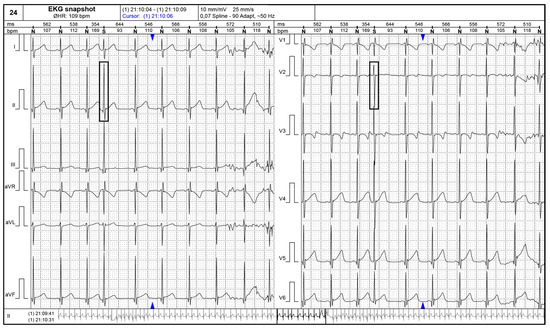

Figure 2 and Figure 3 present supraventricular ectopic beats in a neonate with TS and electrocardiographic changes (short PR interval) in a 2–years–old patient with TS.

Figure 3.

Electrocardiogram showing a short PR interval (80 milliseconds) (black rectangular shape) in a 2–year–old patient with tuberous sclerosis: first figure showing peripheral derivations of the ECG leads and second figure showing the magnified DII peripheral lead.